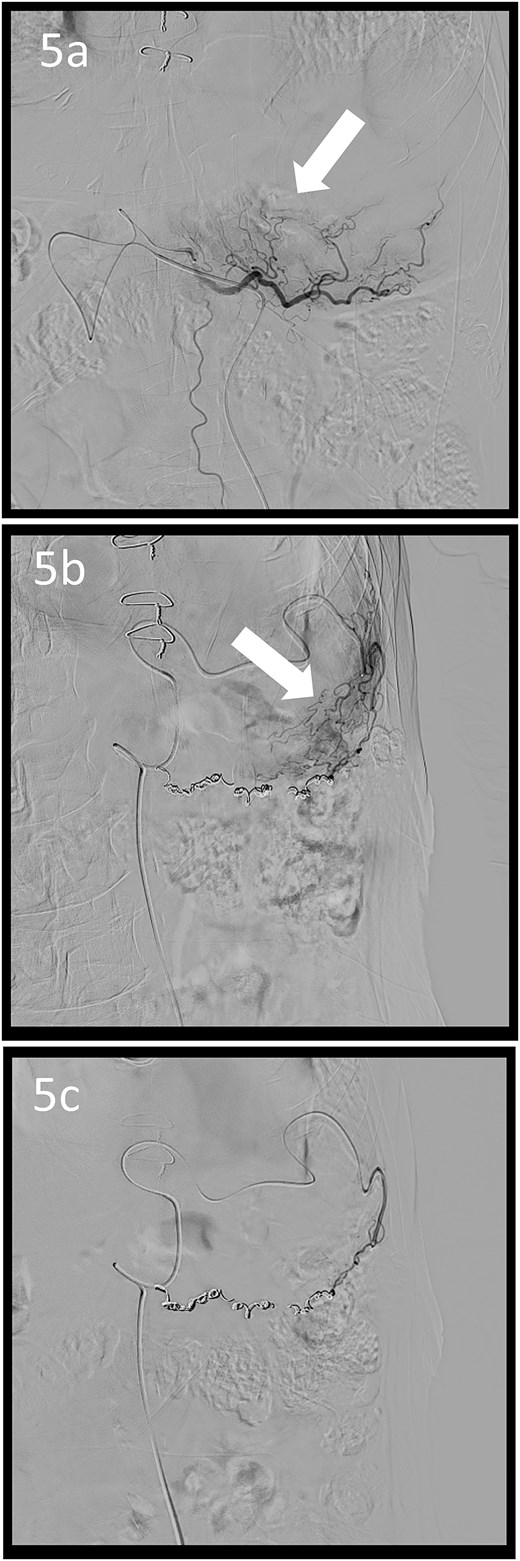

Angiographic images; the right (a) and left (b) gastroepiploic arteriograms showing tumour staining (arrows); (c) both arteries were coil embolized.

A 78-year-old man was transferred to our hospital because of hypovolemic shock. He had already received 10 units of RBC concentrate. His blood pressure was 97/64 mmHg. The patient’s haemoglobin level was 8.2 g/dL. Contrast-enhanced CT showed active contrast extravasation in the stomach (Fig. 4). Emergency angiography revealed tumour staining in both the left and right gastroepiploic arteries, which were coil embolized (Fig. 5). Upper GI endoscopy 2 days later revealed a type 4 tumour without bleeding (Fig. 6). The patient was diagnosed with resectable GC, and underwent laparoscopic total gastrectomy with Roux-en-Y reconstruction and lymph node dissection. The final histopathological diagnosis was T4aN3aM0 stage IIIC. Macroscopic findings revealed a type 4 tumour of the stomach, and histopathological findings revealed that the tumour was a poorly differentiated adenocarcinoma with squamous cell differentiation. All surgical margins were negative. The patient developed a minor leakage that resolved spontaneously. The patient has remained recurrence-free for 12 months.